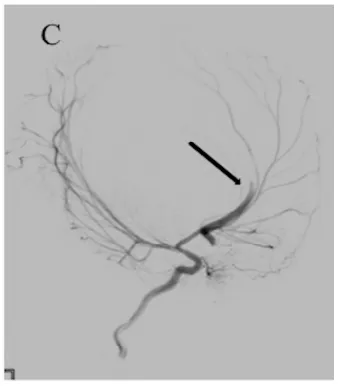

因亨利临床状态稳定,医疗团队决定在其出生后第8天施行数字减影血管造影(DSA),以完成血管内栓塞治疗。术后即刻造影显示主瘘道实现完全闭塞(图2C)。

术后第1天,其神经状态出现轻度恶化。急诊CT显示瘤囊内血栓进展、囊腔较前增大;CTA发现右侧大脑中动脉(MCA)远端新发出一支粗大供血支参与瘘口(图3A),该支在术前DSA中未显影。